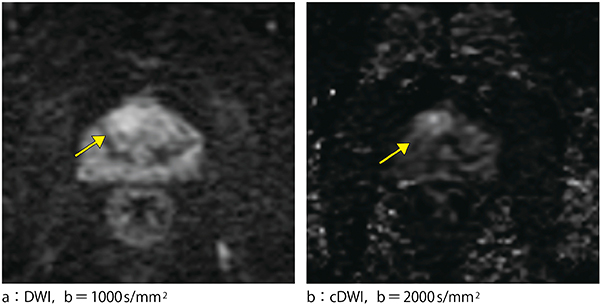

2.前立腺がん

症例は70歳代,男性。既知の膀胱がんに対して術前ステージング目的でMRIを撮像した。当院ルーチンでは,膀胱がんのDWIではb=600s/mm2およびb=1000s/mm2で撮像するようにしている。膀胱がんの所見(非提示)だけでなく,前立腺にb=600s/mm2(非提示)およびb=1000s/mm2(図3 a)で高信号が認められた。ただし,背景組織の高信号に埋もれてわかりにくかったため病変と確信が持てなかった。そのため,b=2000s/mm2のcDWI(図3 b)を作成した。cDWIでは結節状の高信号域が明瞭化したため,前立腺がんを強く疑った。生検で前立腺がんが証明され,膀胱全摘術に加えて前立腺全摘術も施行された。cDWIでの信号異常部が前立腺がん部をよく反映していることが,病理組織像からも判明した。

図3 前立腺がん症例